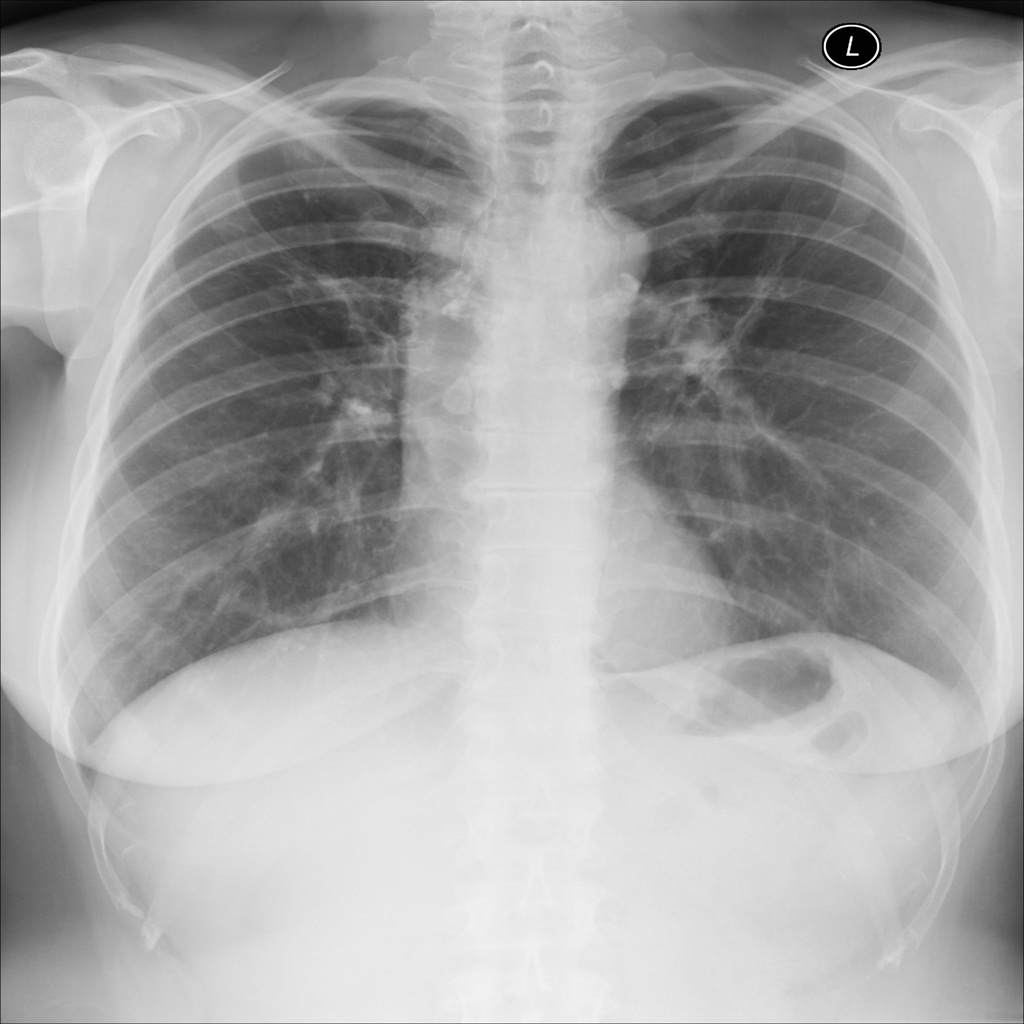

Nodule

A nodule is a small rounded opacity in the lung or chest field. It is a descriptive imaging finding that can be benign or more concerning depending on size, appearance, and context.

Showing up to 90 reference images for Nodule.

PAT-F3E7 · IMG-002Nodule

PAT-F3E7 · IMG-002

PA